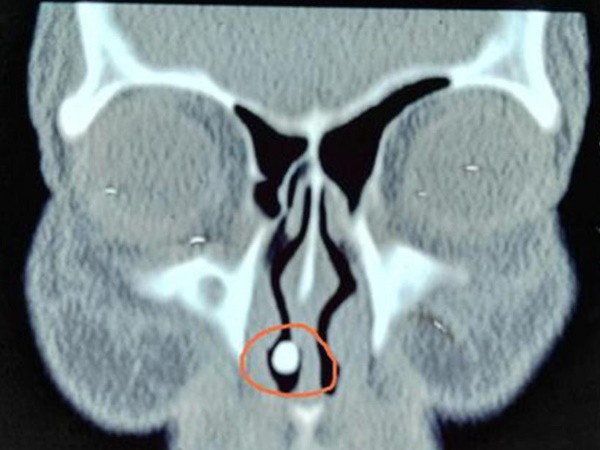

चीन की रहने वाली 57 वर्षीय जिया को काफी सालों से नाक से खून आता था। वो भी इसे आम बात समझ के नजरअंदाज करती रहीं लेकिन जब बात ज्यादा बिगड़ गई तब वो डॉक्टर के पास गईं। डॉक्टर्स ने एक्स-रे किया तो उन्हें उनकी नाक में कुछ दिखा। डॉक्टर्स को लगा कि ये कोई बाहर की चीज है जो नाक में घुस गई है और इसी के कारण इतना खून बह रहा है।

डॉक्टर्स ने इसे निकालने के लिए सर्जरी शुरू की। सर्जरी के दौरान जब डॉक्टर्स को पता चला कि ये कोई वस्तु नहीं, बल्कि जिया का दांत है तो वो भी हैरान रह गए। जिया की नाक में एक दांत उग आया था जो पूरा बढ़ चुका था। डॉक्टरों ने फिर उनकी नाक से दांत निकालने की प्रक्रिया तेज की ताकि उन्हें जल्दी आराम मिले।

डॉक्टर्स के मुताबिक जिया की नाक में ये दांत तभी से था जब वो पैदा हुईं थीं मगर बढ़ना शुरू हुआ प्रेगनेंसी के बाद। जब जिया पहली बार मां बनीं तब नाक में ये दांत बढ़ना शुरू हुआ और सर्जरी के वक्त ये पूरा बढ़ा हुआ था। डॉक्टरों के मुताबिक ऐसे केस काफी कम ही देखने को मिलते हैं।